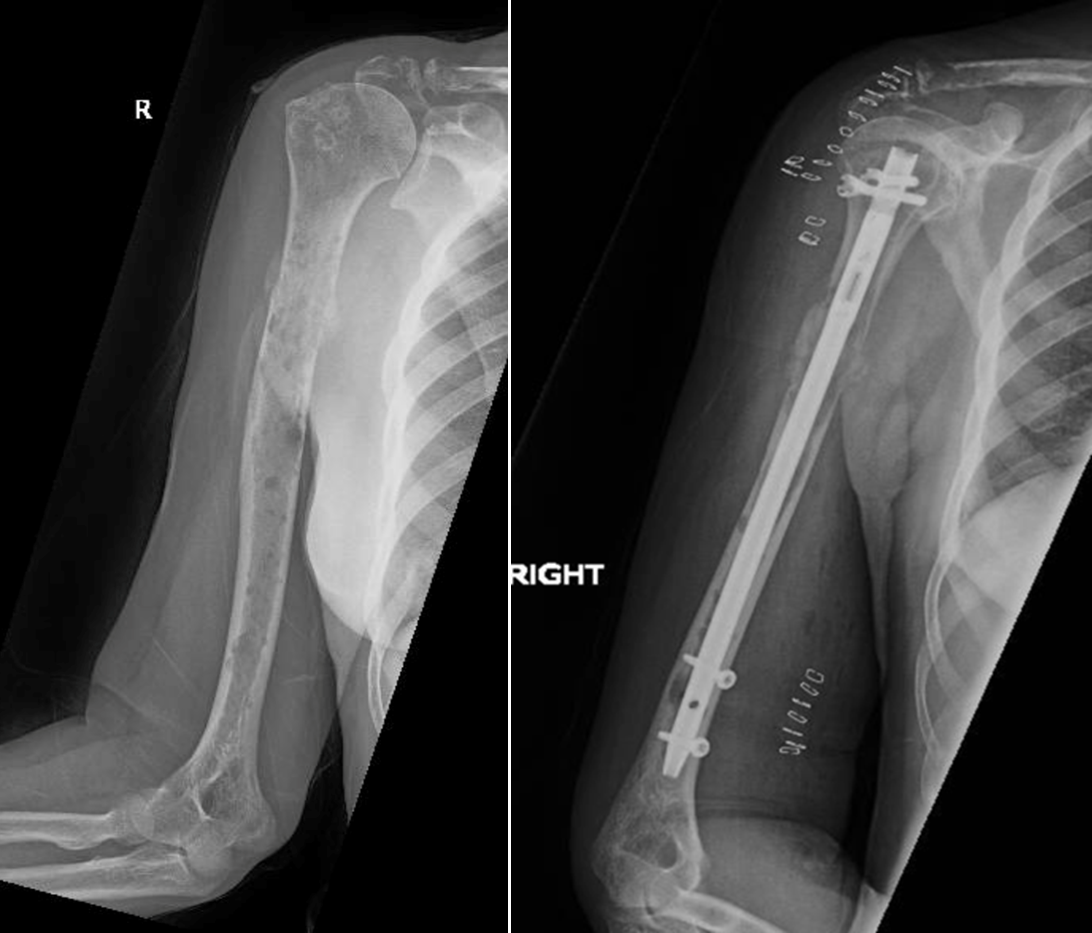

Figure 1: X-ray of thigh bone demonstrating “punched-out” loss of bone on the left; right image demonstrating prophylactic fixation with an intramedullary rod.